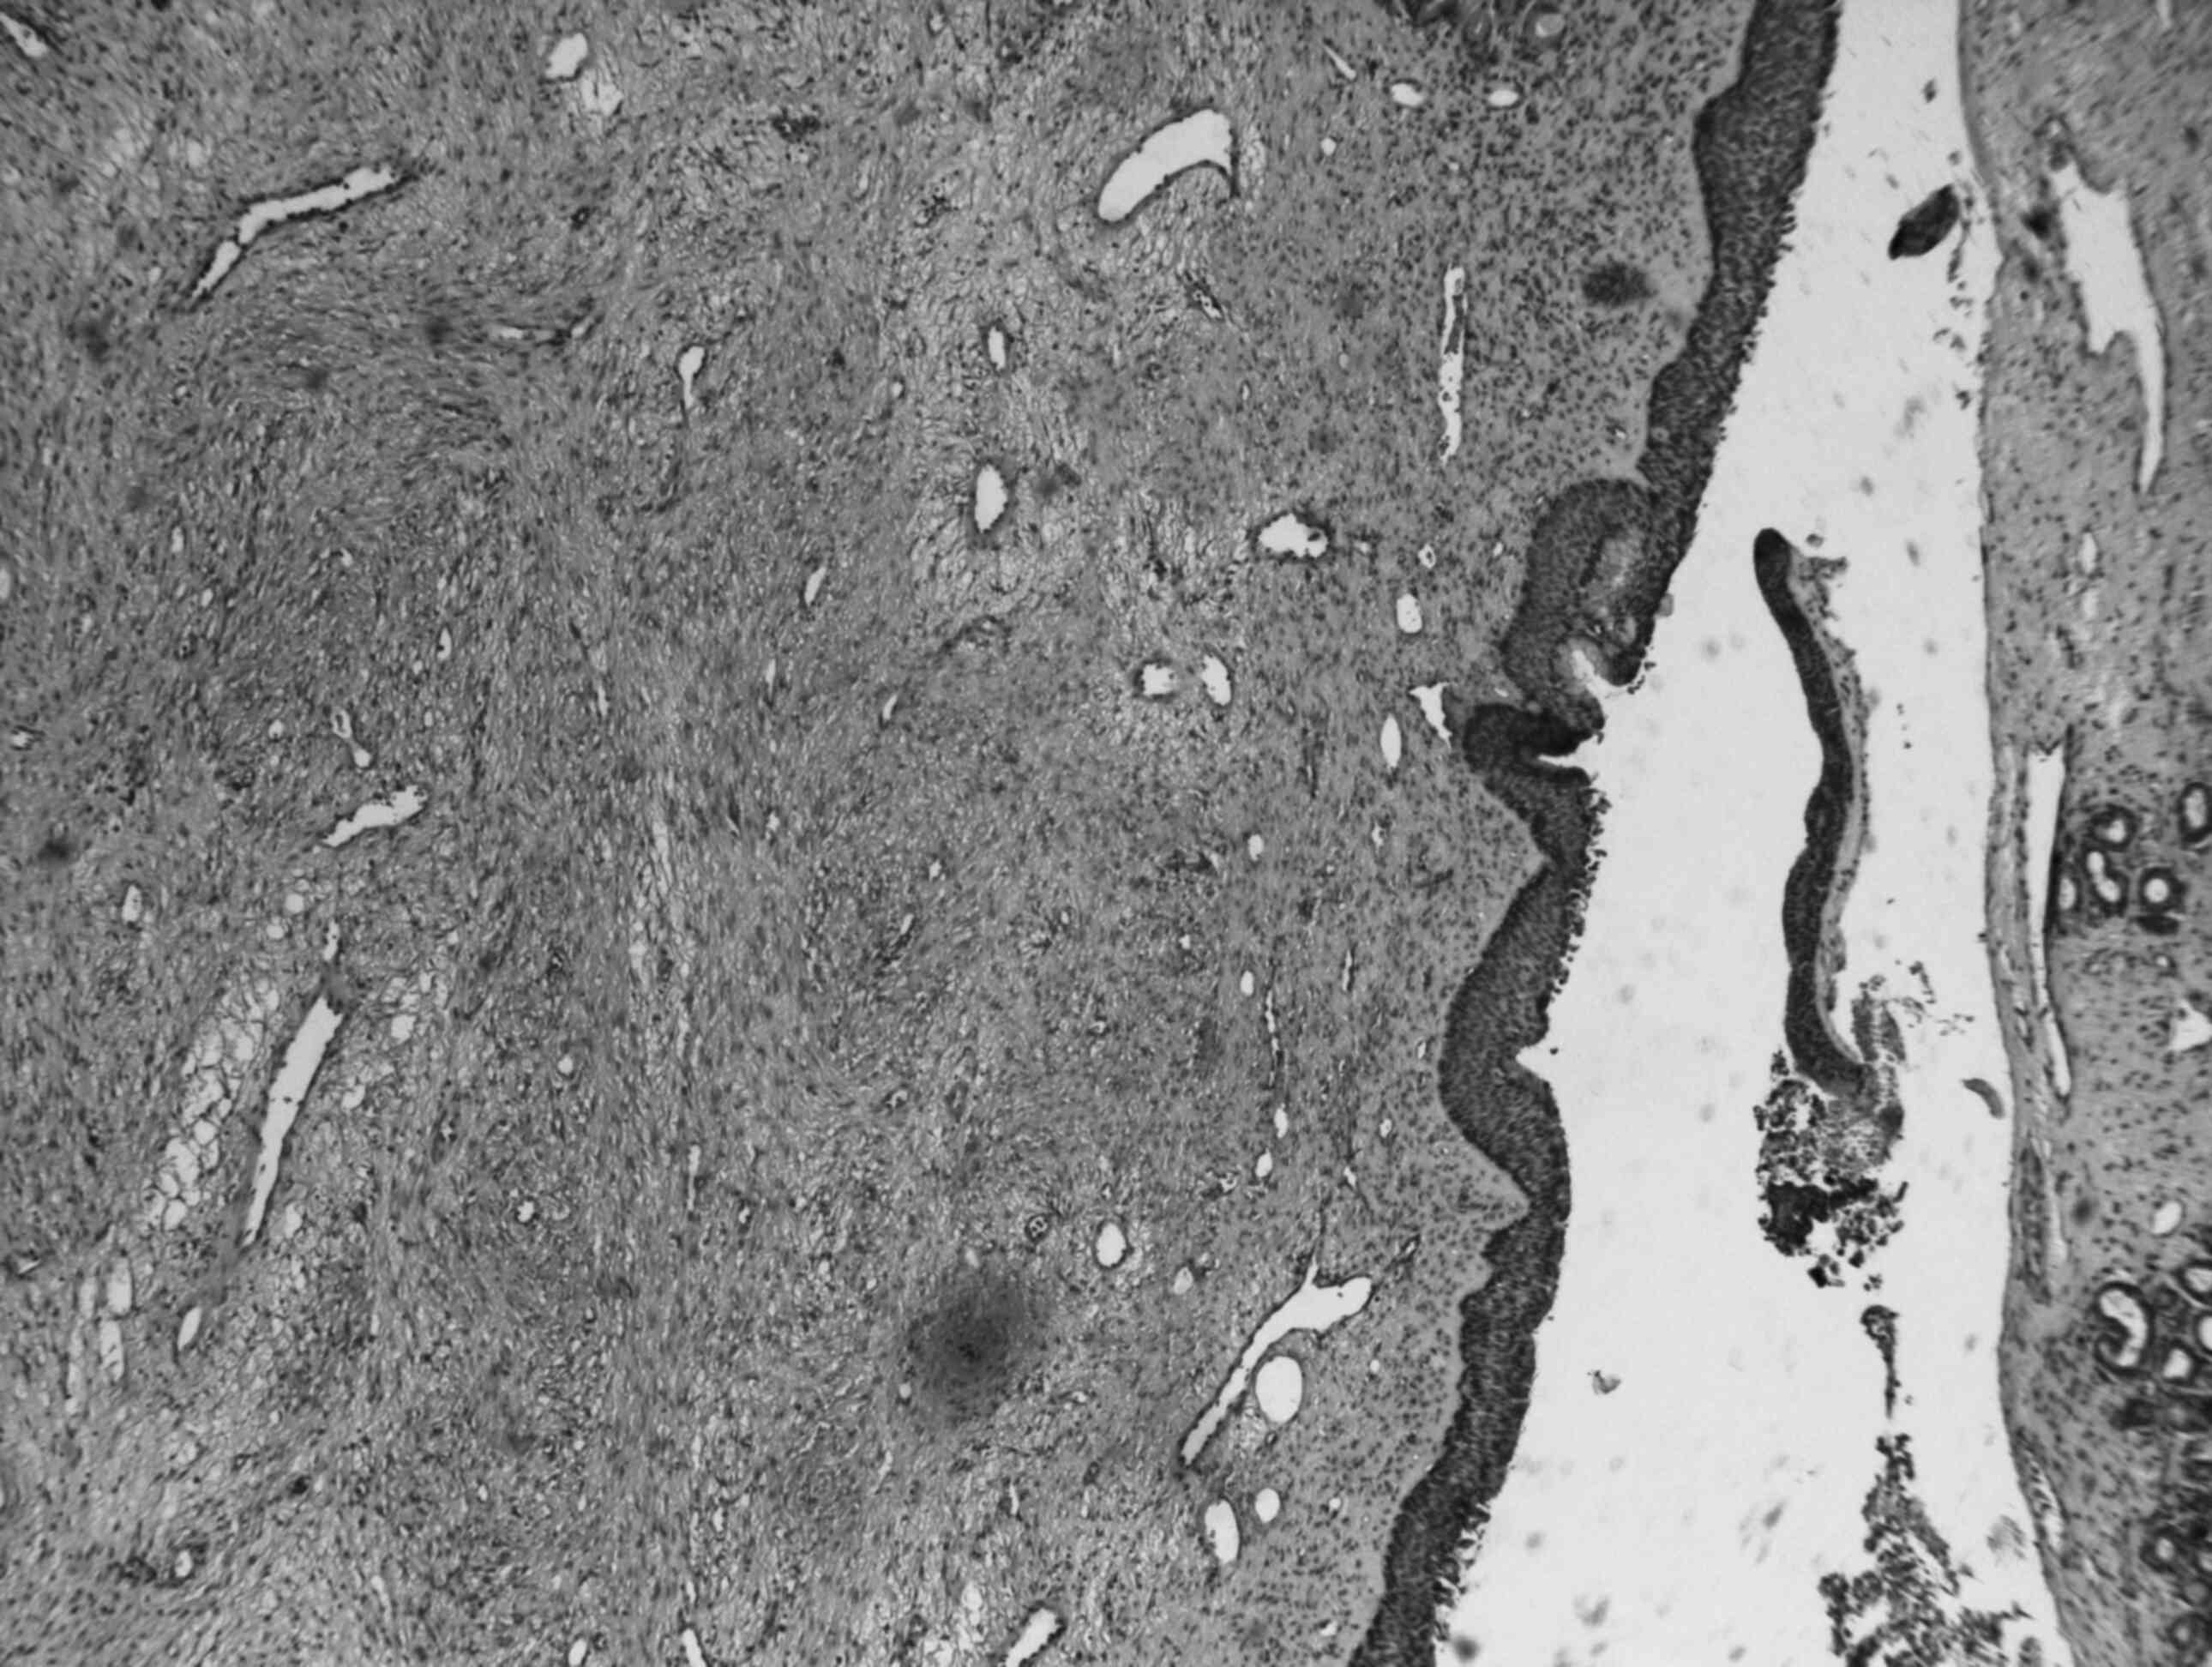

The patient underwent functional transnasal endoscopic removal of the mass under general anesthesia; consistent bleeding occurred during surgery. The mass was entirely removed and was found to be of firm, elastic consistency. The specimen was sent for histological examination; hematoxylin and eosin staining demonstrated that the mass was composed of proliferating blood vessels of variable shape and size, intermixed with a connective tissue stroma. The wall of the vessels was formed only by endothelial cells (CD34+). The connective tissue was fibrocellular, with an irregular pattern and plump fibroblasts (Fig. 2). Immunohistochemical analysis was performed with actin staining for smooth muscle; the perimeter of the mass appeared as a thin rim of smooth muscle cells topped by endothelium (vimentin+ and CD68+). Ki-67 immunostaining demonstrated only a few positive cells, confirming low cell proliferation rate and excluding the possibility of a conventional nasal or antrochoanal polyp with fibrosis (11).

Figure 2.

Histological examination of the specimen (hematoxylin and eosin staining at ×100 magnification) revealed that the mass was composed of proliferation of blood vessels of variable shape and size intermixed with a connective tissue stroma. The wall of the vessels was formed only by endothelial cells (CD34+). The connective tissue was fibrocellular, with an irregular pattern and plump fibroblasts.